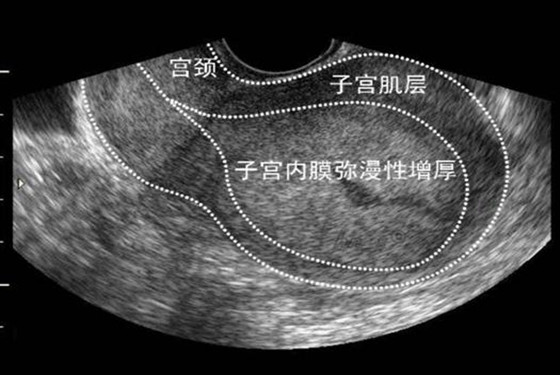

而异常的子宫内膜增生的情况却不同,它是由于妇科疾病或内分泌紊乱所导致的增生情况,具体表现为子宫出血量比较多,来月经的时间比较长,月经迟迟不来的情况等。子宫内膜异常增生时,厚度可达3-12mm不等。更年期和青春期的女性都容易患子宫内膜增生的情况,尤其是肥胖女性患子宫内膜增厚的几率更高,当出现这样的异常增生时,女性会出现白带异常,阴道不规则出血等情况,这样的情况必须引起注意并及时治疗。